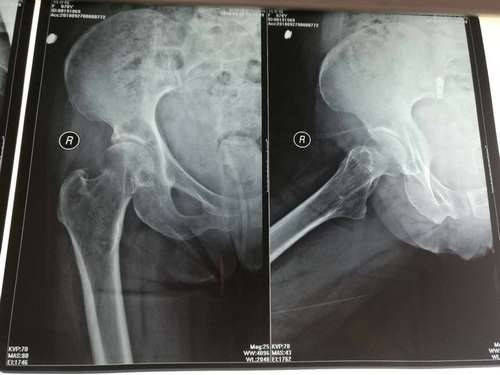

被推倒老人的檢查報告單。朱先生提供

據朱先生提供的老人的診斷報告單顯示,老人78歲,經診斷,右側股骨頸骨折,骨折處周圍組織腫脹。朱先生稱,其奶奶以前股骨沒受過傷,馬上就要進行手術,現在醫藥費也都是家屬自己墊付。